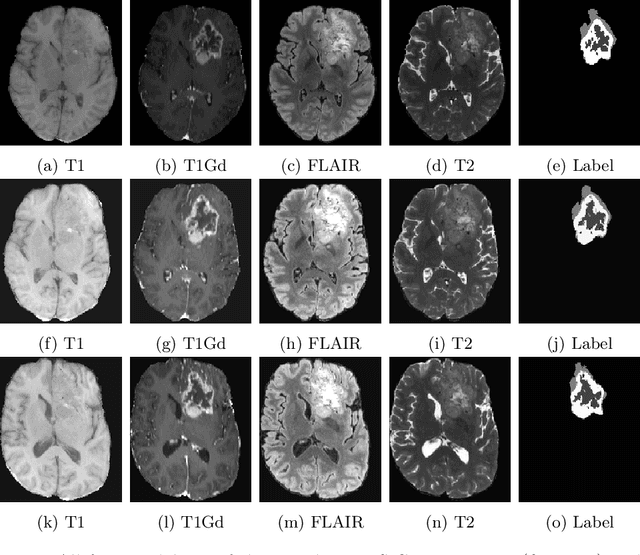

Abstract:Deep Learning is the state-of-the-art technology for segmenting brain tumours. However, this requires a lot of high-quality data, which is difficult to obtain, especially in the medical field. Therefore, our solutions address this problem by using unconventional mechanisms for data augmentation. Generative adversarial networks and registration are used to massively increase the amount of available samples for training three different deep learning models for brain tumour segmentation, the first task of the BraTS2023 challenge. The first model is the standard nnU-Net, the second is the Swin UNETR and the third is the winning solution of the BraTS 2021 Challenge. The entire pipeline is built on the nnU-Net implementation, except for the generation of the synthetic data. The use of convolutional algorithms and transformers is able to fill each other's knowledge gaps. Using the new metric, our best solution achieves the dice results 0.9005, 0.8673, 0.8509 and HD95 14.940, 14.467, 17.699 (whole tumour, tumour core and enhancing tumour) in the validation set.